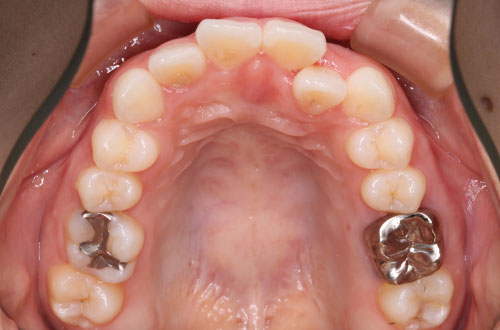

「前歯の部分矯正」~気になる部分だけ治療したい方向け

部分矯正とはその名の通り、「部分的に」歯並びを整える矯正になります。

特徴2「目立たない」装置も/「裏側」の部分矯正も対応

歯の表側に付けるワイヤー矯正の他、歯の裏側に付ける裏側部分矯正、透明なマウスピース矯正(インビザライン)等、患者さんの好みの装置を選択できます。装置によって費用は異なりますのでご相談ください。